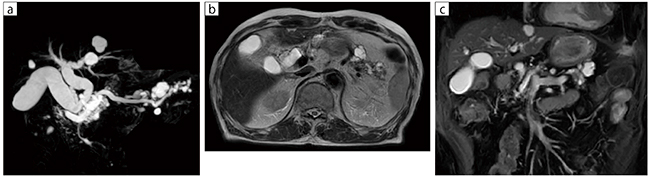

■症例1:膵管内乳頭粘液性腫瘍(IPMN)

80歳代,男性。IPMNのフォローアップで検査実施。MRCPは細かい部分まで描出されている。また,T2強調アキシャル画像は呼吸同期と体動補正RADARを併用しているため,モーションアーチファクトが見られない。

a:3D MRCP,TR/TE=4000/600,スライス厚:2.4mm,FOV:320mm

b:T2WI RADAR,TR/TE=4000/55,スライス厚:6mm,FOV:380mm

c:BASG,COR,TR/TE=3.7/1.8,スライス厚:5mm,FOV:380mm